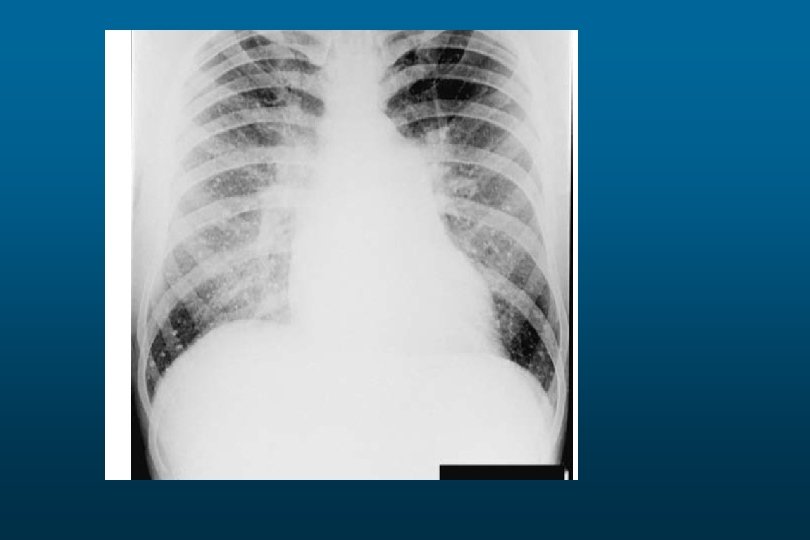

Pulmonary Edema

CHF